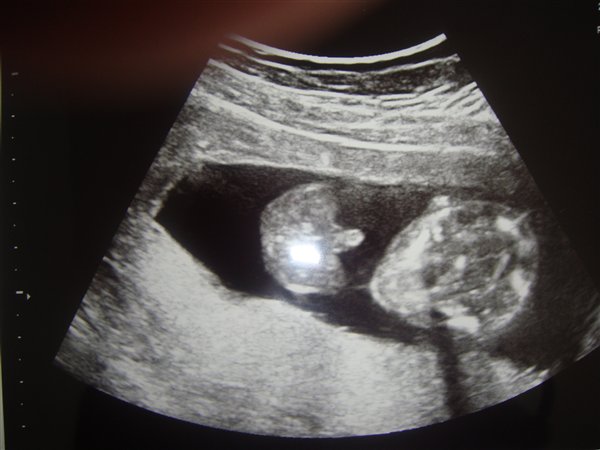

Her er en tydelig tap :-)

Vedhæftede fotos (klik for at se i fuld størrelse)